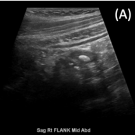

A 12-year-old boy presented with abdominal pain, which he had been experiencing for the past 3 days. When asked to localize the pain with 1 finger, he pointed to the left lower quadrant.